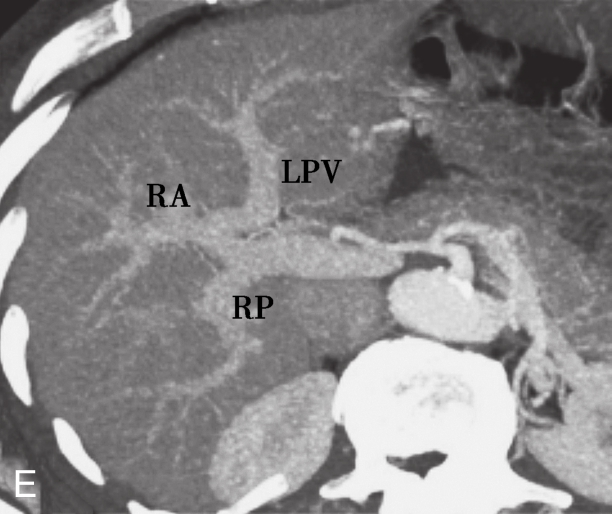

A.冠状面增强CT造影;B.模拟图;C.肝门静脉的三种常见解剖结构;D.Ⅱ型变异:增强造影CT显示肝门静脉分叉成右后、右前肝门静脉和左肝门静脉;E.Ⅲ型变异:增强造影CT显示来自门静脉主干的右后支。

LPV.肝门静脉左支;RPV.肝门静脉右支;RA.右前支;RP.右后支;PV.门静脉;SV.脾静脉;SMV.肠系膜上静脉。